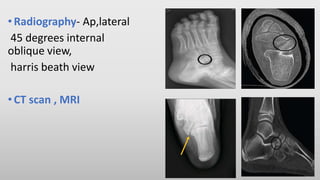

•Radiography- Ap,lateral

45 degrees internal

oblique view,

harris beath view

•CT scan , MRI